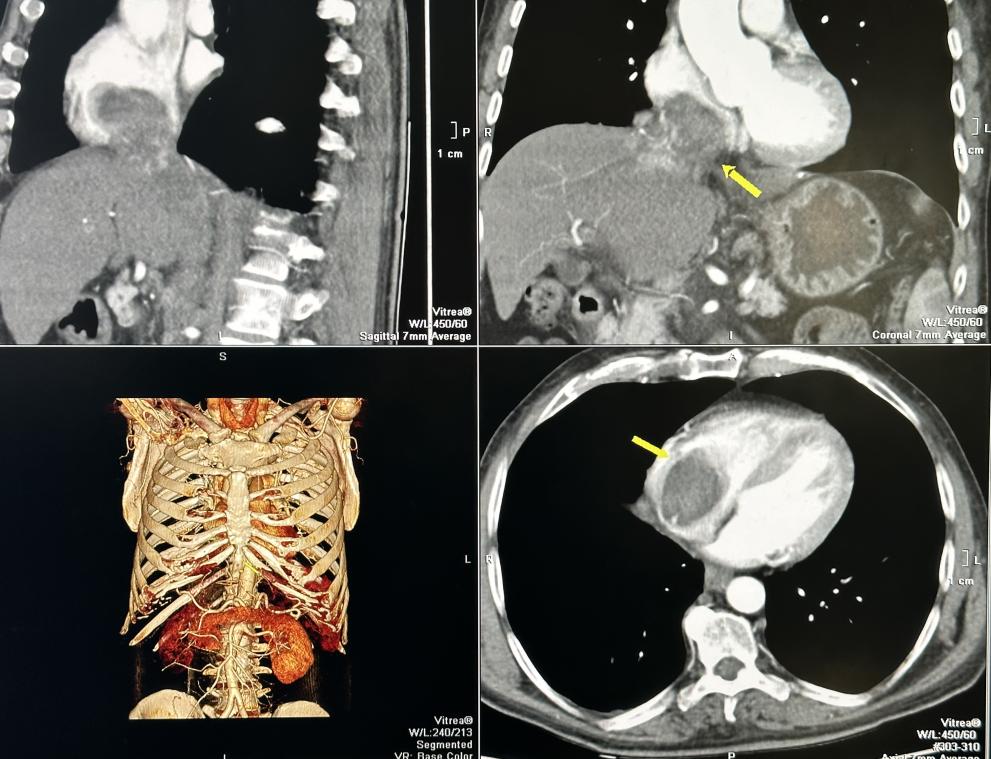

Туморът с размери 7 на 9 см. е заел и извършил съвсем напълно кухината на дясното предсърдие на сърцето и е застрашавал да запуши белодробните артерии и белия дроб.

От болничното заведение прецизират, че след постъпването на пациента е изработен скенер , от който се откриват злокачествените формирания в кухините на сърцето и съществуването на две големи туморни огнища в черния дроб.

Екип на Клиниката по кардиохирургия под управлението на проф. Димитър Петков отстранява изцяло туморите от сърцето и от цялата долна празна вена, намираща се в чернодробния сектор.